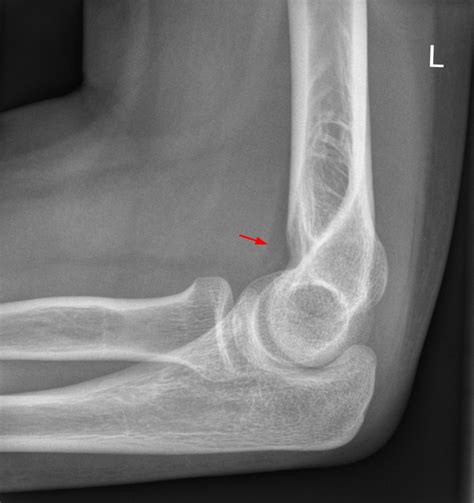

Kompletter Armbruch Gips! Hatte das schon mal wer ...

Kompletter Armbruch Gips! Hatte das schon mal wer ... from images.gutefrage.net